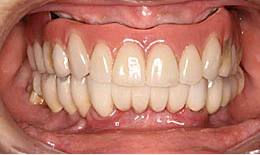

治療後

保存困難な歯を抜歯後、インプラントを7本埋め込み、ボーンアンカードブリッジを装着した

保存困難な歯を抜歯後、インプラントを5本埋め込み、セラミックスクラウンを被せた